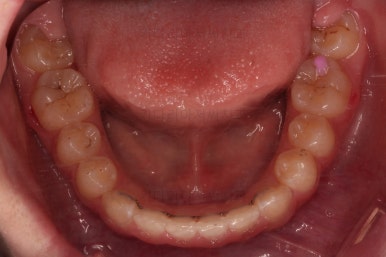

초진 시 입안의 모습입니다.

앞니가 안으로 굽어 들어간 양상인데요. 흔히 "옥니"라고 표현합니다.(뻐드렁니의 반대개념)

전반적으로 치열이 삐뚤삐뚤하고요.

그리고 전반적으로 아래 치열이 윗니에 비해 뒤로 밀려 있어서, 어금니의 맞물림이 좋지 못하고 듬성듬성해 보이는 상황이었어요.